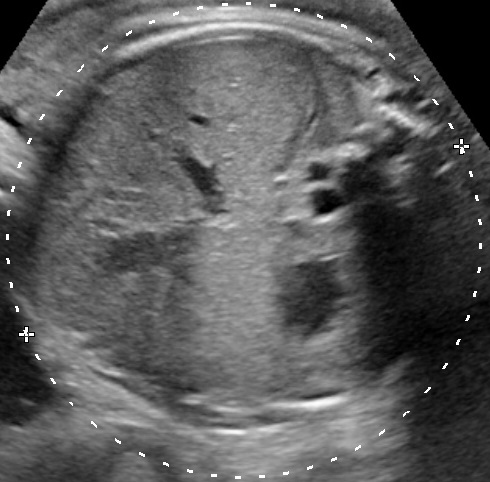

The gestational week does not influence the diagnosis of polyhydramnios. The size of the uterus could be suggesting of this condition, however the diagnosis should be made during ultrasound examination. There are two common ways to estimate the volume of the amniotic fluid:

- Single Deepest Pocket (SDP). A vertical measurement in the deepest amniotic fluid pocket. Values below 2 cm indicate oligohydramnios, values over 8 cm indicate polyhydramnios (8-11: mild, 12-15: moderate, > 16: severe). In multiple gestation, a range of 3–8 cm is defined as normal. Another technique is the

- Amniotic Fluid Index (AFI). This is the sum of vertical measurements of all four quadrants (polyhydramnios usually >24).